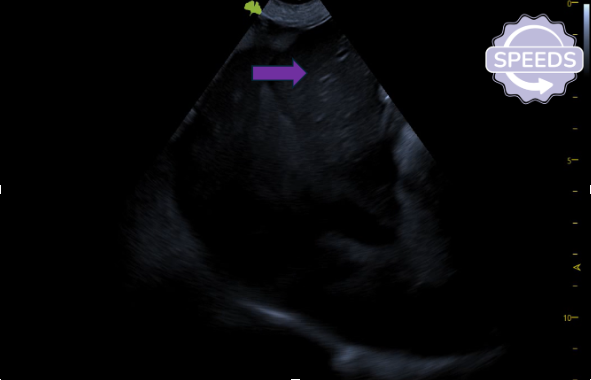

Hypoechoic liver with bright portal veins (purple arrow).